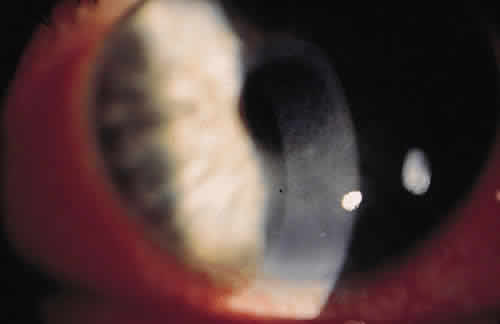

Syphilis is caused by the spirochete Treponema pallidum. Ocular findings can be seen in secondary syphilis in the form of iritis or anterior uveitis.52 Circulating immune complexes containing treponemal antigens and fibronectin combined with antibody and complement are present in this stage of infection and are thought to be responsible for the clinical findings.53 Syphilis may also present as interstitial keratitis in the congenital form (Fig. 6) or as a late finding in secondary syphilis with corneal scarring.54 There is a cell-mediated and humoral response to T. pallidum. The humoral response consists of nonspecific antibodies (reagins) that react to cardiolipin and specific antibodies that react to specific components on treponemes. These responses lead to an edematous cornea diffusely infiltrated with lymphocytes.49

Fig. 6. Interstitial keratitis.